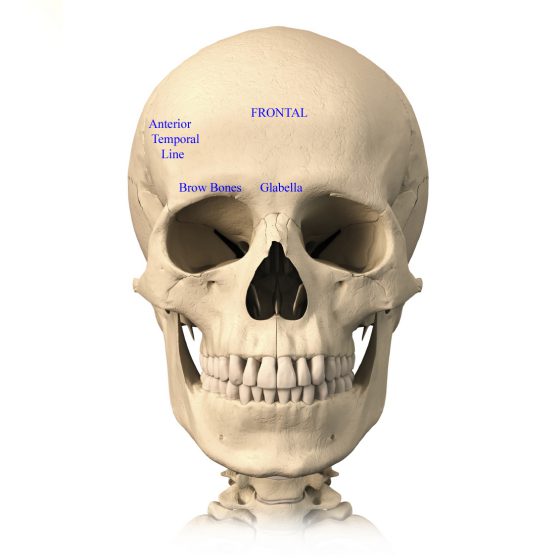

Prepare to be captivated by List, a showcase of real human skull front view black and white imagery powered by ieltschampions.edu.vn. More related visuals are below.

real human skull front view black and white

Posts: real human skull front view black and white